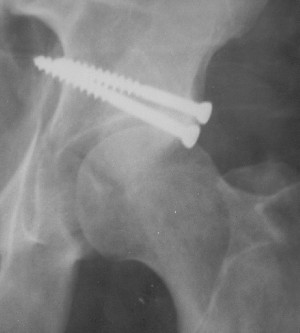

19/05/03

Больной 18 мая 2003 года в автоаварии получил перелом левой вертлужной впадины, вывих бедра. Госпитализирован в один из стационаров области.Вывих вправлен. В последствии бедро вывихивалось еще дважды. На консультацию был представлен снимок от 19.05.03г., больной переведен к нам 3.06.03г. Снимок при поступлении - перелом впадины, задне-верхний вывих бедра. 05.06.2003 г. выполнено открытое вправление вывиха левого бедра и остеосинтез стенки вертлужной впадины двумя винтами. Послеоперационный период без осложнений. Объем движений в левом тазобедренном суставе восстановился полностью. Выписан на амбулаторное лечение в удовлетворительном состоянии с рекомендациями 3 месяца ходить на костылях без нагрузки на оперированную конечность. На контрольных рентгенограммах левого тазобедренного сустава 13.10.2003 г. - признаки консолидации перелома; плотность, форма головки и состояние суставных поверхностей удовлетворительные. Разрешена дозированная осевая нагрузка, на конечность с использованием дополнительной опоры. 19.12.2003 г. больной обратился с жалобами на боли в левом тазобедренном суставе. На рентгенограммах левого тазобедренного сустава 19.12.2003 г., 20.02.04г. - асептичекий некроз головки бедра. 5.04.04г. - эндопротез. Сейчас ходит без трости, не хромает. Особенность эндопротезирования - при удалении винтов прослежена линия перелома заднего края впадины и предложено установить чашку несколько меньшего диаметра, чтобы она была покрыта несломанной частью.